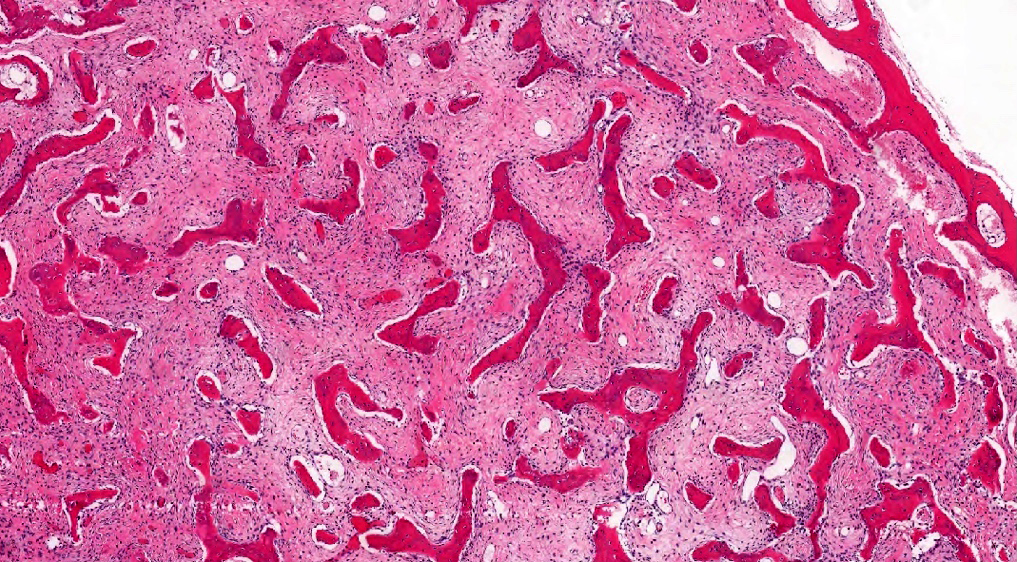

Microscopic (histologic) description

- Branching and anastomosing irregular trabeculae of woven bone ("C" and "S" shapes) with no conspicuous osteoblastic rimming

- No / rare osteoclasts

- Intervening fibrous stroma containing cytologically bland spindle cells, without prominent cytologic atypia

- Mitotic figures rare

- Stromal changes, including myxoid change and fatty metaplasia, may be seen in some cases (BMC Musculoskelet Disord 2003;4:20)

- Secondary aneurysmal bone cyst-like changes may also be seen (Turk Patoloji Derg 2018;34:234)

- Fibrocartilaginous dysplasia: uncommon variant containing variable proportions of cartilaginous differentiation and enchondral ossification (Am J Surg Pathol 1993;17:924)

- Growing collagen (Sharpey's fibers) may form perpendicular to the sites of bone formation but are not essential for diagnosis (Oral Dis 2017;23:697)

Microscopic (histologic) images